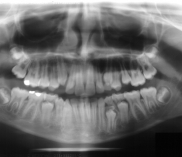

Chirurgia dentystyczna zajmuje się leczeniem operacyjnym jamy ustnej, zębów i tkanek otaczających. Znaczna większość zabiegów z zakresu chirurgii stomatologicznej jest wykonywana w znieczuleniu miejscowym .Dental Park jako jeden z nielicznych oferuje również wykonywanie zabiegów pod narkozą. Najpowszechniejszym zabiegiem z zakresu chirurgii stomatologicznej jest usunięcie zęba czyli ekstrakcja, ale chirurgia stomatologiczna to także zaawansowane zabiegi jak implanty czy wyłuszczanie torbieli kości.

Chirurg stomatolog posiada wieloletnie doświadczenie i w swojej karierze spotkał się z najtrudniejszymi przypadkami. W gabinecie wykonywane jest usuwanie zębów w znieczuleniu miejscowym oraz w narkozie co zapewnia całkowicie bezbolesny zabieg. Pracownia stomatologiczna usuwa zęby mądrości, złamane korzenie. Bardzo często naszymi pacjentami są osoby, które usuwają zęby ze wskazań ortodontycznych. Wykonujemy również zabiegi odbudowy kości jako przygotowanie do leczenia implantologicznego. Nasi pacjenci mogą zawsze liczyć na szybką pomoc w przypadku ropnia, ostrego bólu lub urazu. Chirurg stomatolog zajmuje się wszystkimi nawet najbardziej skomplikowanymi przypadkami.